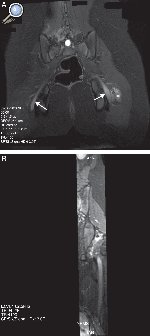

Entre las neuropatías de los nervios de las extremidades inferiores, las neuropatías posturales pueden ocurrir en una variedad de posiciones, las más descritas la de litotomía y la de sentado. Estas causas de lesión del nervio ciático son prevenibles y suelen ocurrir por descuido intraoperatorio, ya sea porque el paciente permanece demasiado tiempo en la misma postura, o por error en el posicionamiento. Esto ha tenido un alto impacto médico-legal29, 30, 31. En ambas posiciones, las mismas fuerzas que contribuyen a la lesión por estiramiento del grupo muscular de los isquiotibiales (por ejemplo, bíceps femoral), pueden generar el estiramiento del nervio ciático. Debido a que la posición afecta a la vez a ambos miembros, la afectación del nervio ciático puede ser bilateral. El trauma en el músculo piriforme genera espasmo o contractura muscular y, secundariamente, lesión del nervio por compresión y/o estiramiento32. Los hallazgos en RM, teniendo en cuenta el antecedente clínico, son muy sugestivos. Las imágenes muestran un engrosamiento fusiforme del nervio a su paso por la escotadura ciática, un foco de contusión en los músculos piriforme, cuadrado femoral y glúteo, así como cambios en los planos grasos adyacentes. La captación de contraste por estas estructuras se explica por el componente inflamatorio agudo del paquete vásculo-nervioso de la vaina neural, junto con la compresión muscular adyacente (Figura 4).

Figura 4. Niña de 13 años con antecedente de cirugía en posición sentada durante 8h. A) Secuencia IDEAL ponderada en T2 con saturación de la grasa en el plano coronal. Se observa un aumento de la señal y engrosamiento difuso de ambos nervios ciáticos, con predominio en el lado izquierdo (flecha). Se acompaña de edema de las partes blandas adyacentes en el lado izquierdo (asterisco). B) Reconstrucción MPR curva en el eje longitudinal del nervio.